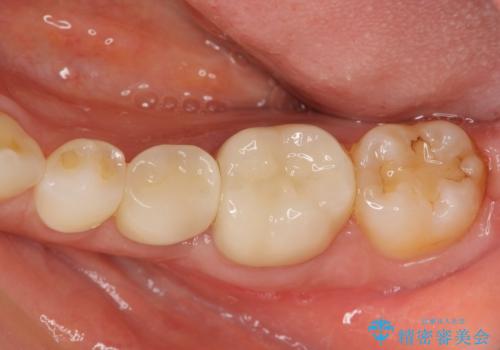

詰め物を除去したのち、虫歯を丁寧に除去することで神経を保存しながらセラミッククラウンによる補綴治療を行うことができました。

- 24.2万円(仮歯・ジルコニアクラウン×2)費用は治療当時の料金となります

外から見て白くきれいな修復が為されていたとしても、内部で虫歯が再発していることは多々あります。

違和感を感じたら早期にX線検査を行い、神経が保存できるうちに治療を行うことが重要です。